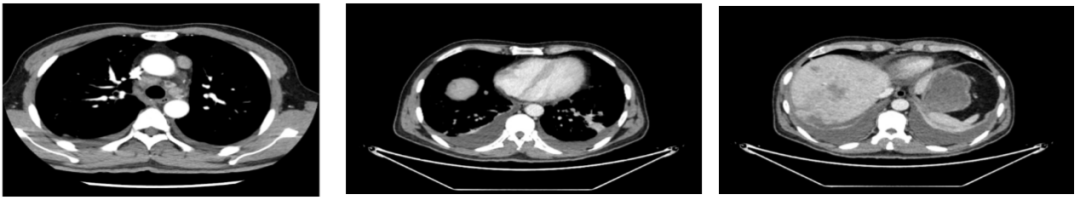

2018-11-14 CT(8周期化疗后):PD?

△基线水平

△治疗后